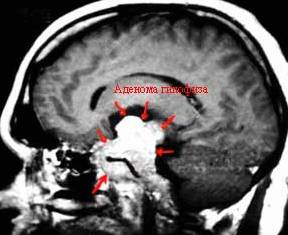

Специфической чертой такого новообразования считается гиперсекреция гормонов гипофизарной области. Аденома гипофиза определяется у 15% онкобольных с опухолью центральной нервной системы.

Это генетически передаваемая опухоль, которая состоит из эмбриональных тканей гипофизарной области.

Диагностика рака мозга, в большинстве случаев, не представляет особенных сложностей. Диагностика данного поражения базируется на результатах компьютерной и магнитно-резонансной томографий. При этих исследованиях врач оценивает состояние мозговых тканей с помощью цифровой обработки послойного сканирования черепной коробки.